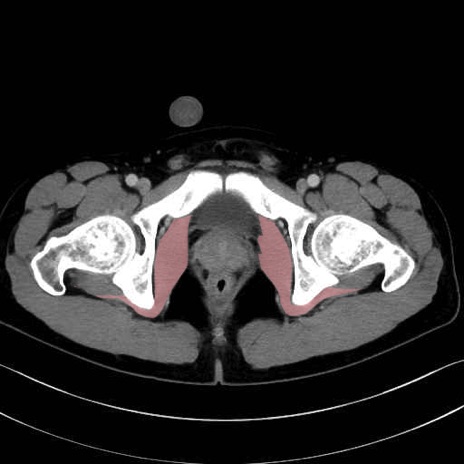

内閉鎖筋(obturator internus) のCT画像の解剖

内閉鎖筋 (Obturator internus)